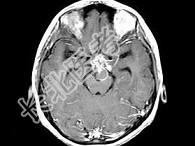

- 单项选择题女,18岁, 发育不良伴口渴,多饮、多尿10余年, 根据所提供图像,最可能的诊断是 ( )

C、颅咽管瘤